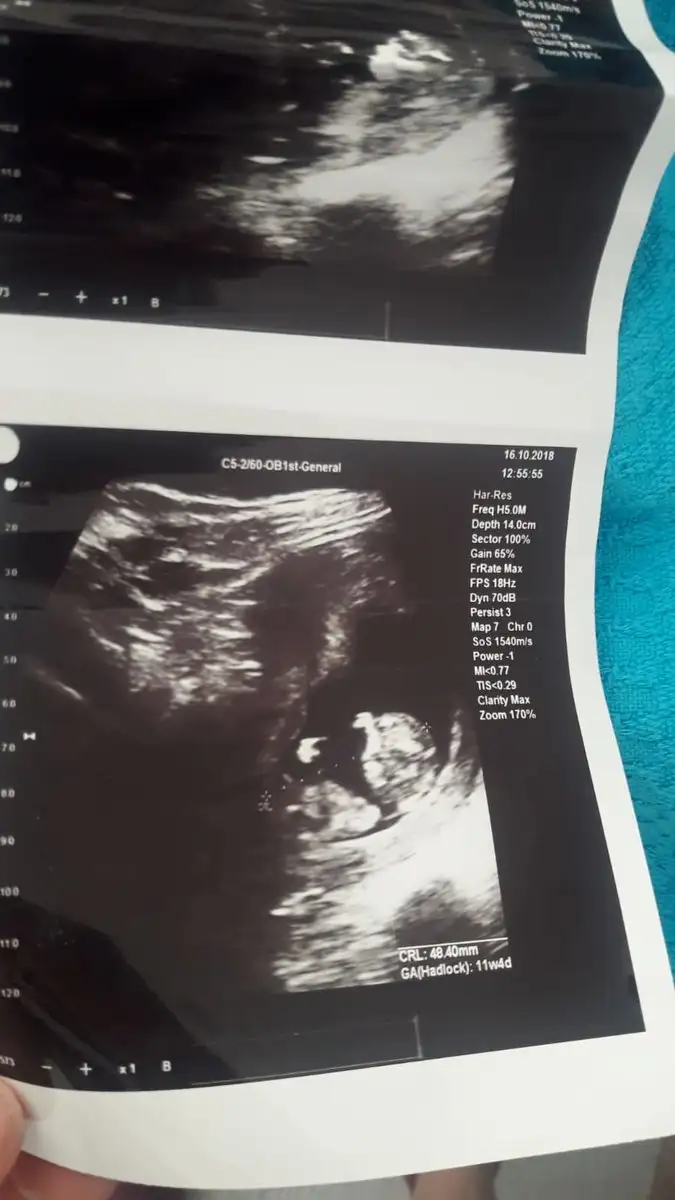

• bebişim 3.webp

bebişim 3.webp

33,2 KB · Görüntüleme: 122

14 haftalik canim ama devlette biraz daha ileri cikti . Ozel doktoruma gore soyluyorum. Insallah canim. Insallah tez vakitte sizde saglik ve hayirlisi ile gorursunuz . Ve hepimiz de kucagimiza hayirlisi ve saglikla aliriz insallah . Erkege kiza nasil benzetiyosunuz o kadar baktim nesinden anliyosunuz :))))